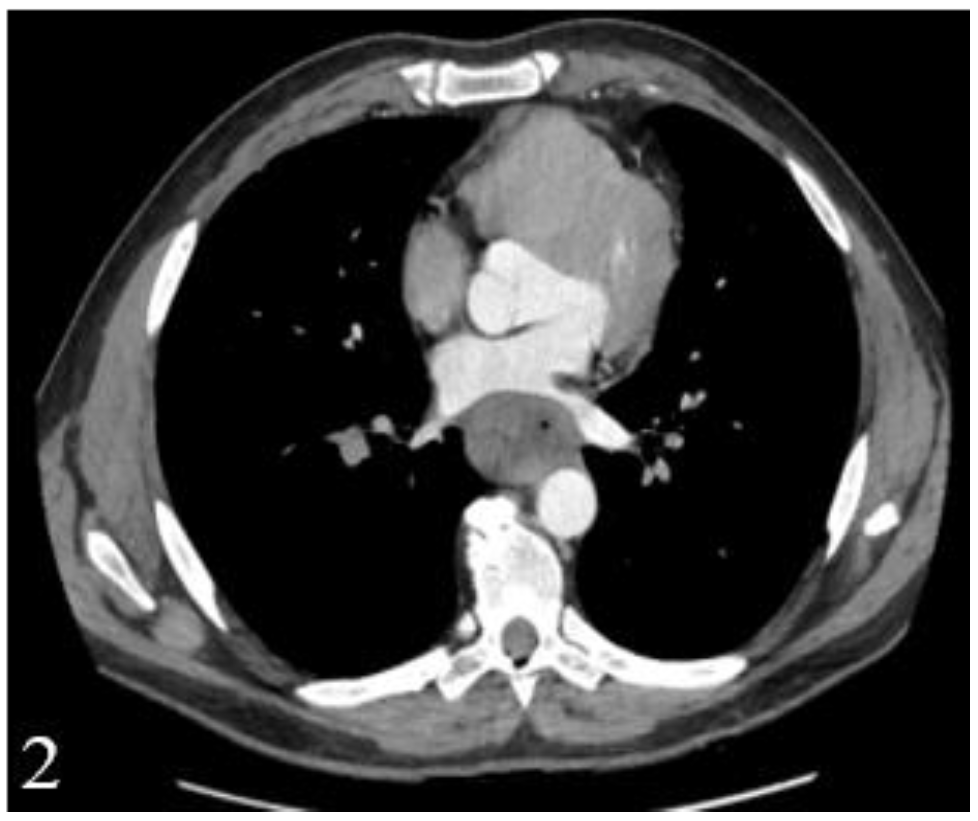

This finding has a major influence on the thoracotomy decision, which has to be taken not only based on computed tomography, due to the low diagnostic accuracy (Figure 1 and Figure 2).

Figure 2.

Postcontrast CT, arterial phase, axial plane. Stenosing tumor of the distal esophagus and gastroesophageal junction that is tangent to the intrathoracic descending aorta and partially compresses the left pulmonary vein with no obvious signs of macroscopic invasion.